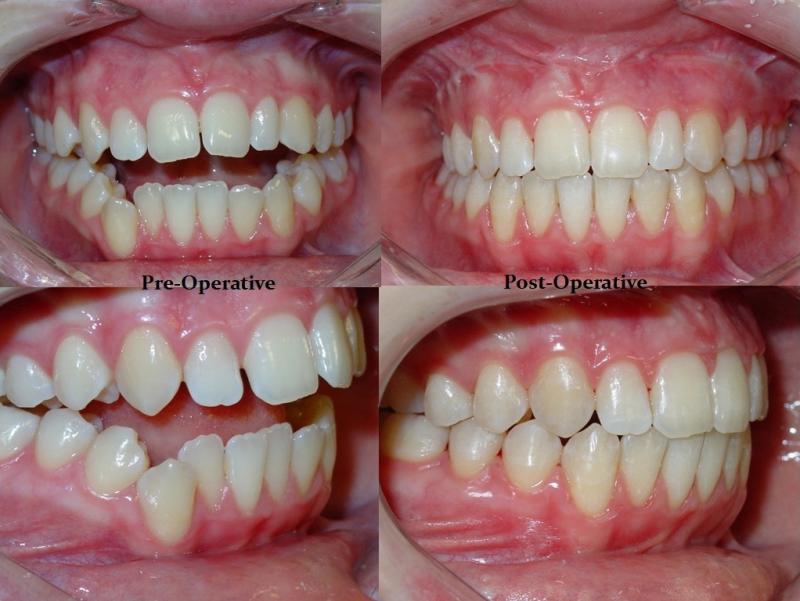

Diagnosis and treatment of dysgnathia, and orthognathic reconstructive surgery, genioplasty, maxillo-mandibular advancement/set-back, and surgical correction of facial asymmetry (See Images Below)

Orthognathic Surgery (Class II)

Orthognathic Surgery (Class III)

Orthognathic Surgery (Class II with 'Gummy Smile')